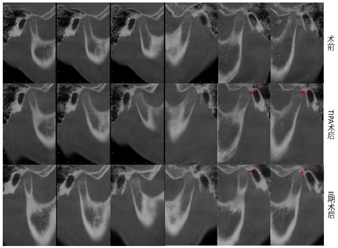

CBCT牙齿截图显示:上下前牙未见明显牙根吸收,上下前牙牙根位于骨松质内(图7)。关节截面显示:TIPA治疗后髁突表面发生功能性改建;髁突位置发生后退,关节窝随之发生相应改建。Ⅱ期治疗后髁突位置稳定,关节间隙恢复正常(图8,图9,图10)。治疗前、中、后头影测量结果见表1,矫治器前后头影描绘重叠图见图11。

2.TIPA是一种新型的功能矫治器[3],主要结构是双侧后牙合垫区由前下后上的两长斜导面组成,利用咀嚼力"渐进式"逐渐诱导下颌骨(骨、牙槽骨、牙)向后运动、上颌骨(骨、牙槽骨、牙)向前运动以及诱导髁突、关节窝发生生理性改建(图9、图10)。相较于头帽-颏兜(Facemask,FM)、Frankel Ⅲ(FR Ⅲ)、反式Twin Block(RTB)、双阻板磁力矫治器、骨性支抗弹性牵引等传统早期矫治装置,其主要针对于以下颌发育过度为主的骨性Ⅲ类生长期错合畸形,独有的长斜面结构有利于咀嚼、前伸和侧方运动,力更接近生理性,患者易适应和配合,且不要求后退下颌重建上下颌位关系,制作简单。术后患者矫治效果良好,锥形束CT重叠观察到髁突及关节后区发生生理性改建(图10),这与笔者团队的之前TIPA能持续性引起关节区不同区域的不同改建的研究一致[4,5,6]。